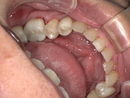

診察の結果、脱落した詰め物の周囲だけでなく、隣接する歯との適合性も著しく低下していました。

二次虫歯(再発虫歯)の進行: 詰め物と歯の隙間から菌が入り込み、内部で虫歯が広がっていました。

歯周病リスクの増加: 段差がある箇所にプラーク(歯垢)が溜まりやすく、歯茎の炎症を引き起こしていました。

噛み合わせの不調: 詰め物が欠けた状態で放置されていたため、反対側の歯に負担がかかっていました。

このまま「その場しのぎの補修」を繰り返しても、数年後にまた再発する可能性が高いと判断し、「精度」「耐久性」「審美性」のすべてを満たすジルコニアセラミッククラウンをご提案しました。